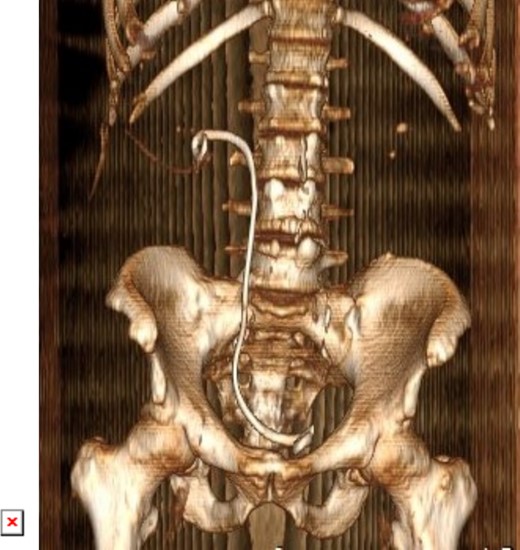

Postoperatively, a low dose non-contrast CT scan confirmed stone clearance (Fig. 6). Subsequent outpatient follow-up with renal ultrasound showed no residual hydronephrosis. The newly inserted double J stent was removed three weeks after the percutaneous nephrolithotomy procedure.

3D constructed image of postoperative low dose non-contrast CT scan showing stone clearance and newly inserted DJ stent in-situ.